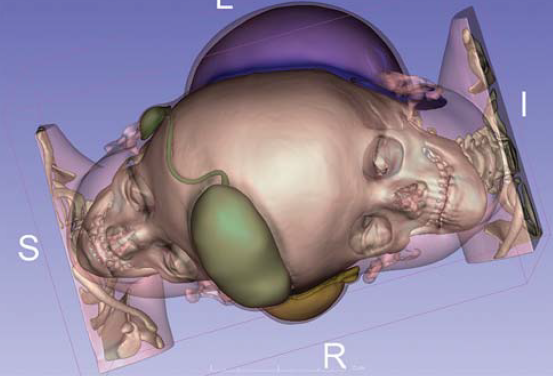

3/a,b. ábra.

Az agyak vénás hálózatának 3D rekonstrukciója az okklúzió egyes fázisaiban.

Az occlusio után sem az altatás idején, sem az ébredés után, sem pedig a következő időszakban nem kivánatos esemény nem történt. Tehát az ikrek sem agyi oedema, sem bármely neurologiai deficit jelét nem mutatták. Az egyik gyermeknél (Rukaya) kialakult magas láztól eltekintve, a beavatkozás nem okozott iatrogén ártalmat. A később elvégzett MRI angiografia kimutatta az embolizáló anyagot a lezárt sinusban (3/a,b. ábra).

Itt kell megemlítenünk az eddig, sziámi ikreknél még ebben a részletességben nem alkalmazott módszert, a 3D modellezést, amelynek segítségével további, alapvetően fontos információhoz jutottak részben az első fázis sikere szempontjából, de később is. A magyar team tagja lett Czeibert Kálmán, aki a számítógépes grafika és az ennek alapján készített 3D modellek szakembere volt. Ő eredeti végzettsége szerint állatorvos, aki neuroanatómiai témájú PhD-munkája során ismerkedett meg ezzel a technikával. Jelen esetben az ismételt képalkotó eljárások felvételei alapján szerkesztett modelljeivel plasztikusan tudta ábrázolni az ikrek agyát és annak ereit, több síkból lehetővé téve tanulmányozásukat, ezáltal a műtét begyakorlását. Az ő segítségével derült ki, hogy Hudák István beavatkozása után még mindig van egy olyan nagyobb nyitott véna a két agy között, amelyet szintén el kell zárni. Őt tarthatjuk e történet negyedik főszereplőjénnek, vagyis kulcsemberének, aki nemcsak új módszert hozott be a vizsgálóeljárások közé, hanem azért is, mert átlagon felüli tehetségével, eredeti meglátásaival, jelentős része volt a projekt sikerében. Ez volt az első eset, hogy MRI és CT angiográfiás felvételekből speciális programokkal felfedezte és pontosan lokalizálta, valamint modellen a valóságban is megjelenítette azt az intracerebrális vénás sinust és ágrendszerét, amely az első embolizáció után nyílt meg, s amit a korábbi vizsgálatok nem mutattak, de nem is mutathattak ki, mivel elképzelhető, hogy az első beavatkozás idején még nem is léteztek (vagy nem voltak láthatóvá tehetőek a képalkotó eljárásokkal).

A februári beavatkozás után 6 hónappal elvégzett kontroll vizsgálat szerint ugyanis a megváltozott áramlási viszonyok miatt új véna, egy belső vénás sinus alakult ki a két összefekvő agyfelszín között, amelyet az orvosok intracerebralis felső sagittalis sinusnak neveztek el. Ez a lelet valószínűleg igen súlyos, esetleg fatális, későbbi intraoperatív vérzéses szövődmény lehetőségét előzte meg. Czeibert Kálmán új módszerével, kifinomul agyi struktúrák különleges megjelenítésével és szerepüknek hangsúlyozásával tehát valószínűleg megmentette az ikrek életét. A második (kiegészítő) occlusiot kizárólag emiatt határozták el és ennek céljából Hudák István és Csókay András ismét Dhakába utaztak és 2018 augusztus 19.-én sikerrel megtörtént a második embolizáció is (4. ábra).